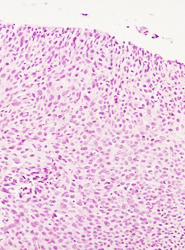

• Lesión de alto grado, con anisocitosis y anisocariosis severas, hipercromasia nuclear, con algunas células apoptoticas.

• Células escamosas neoplasicas, con anisocitosis, anisocariosis, severas, con pérdida de la cohesividad y orientación celular.

• Atipias nucleares severas en una neoplasia intraepitelial cervical de alto grado, llama la atención las células apoptoticas.

• Anisocitosis y anisocariosis severas, hipercromasia nuclear, perdida de la cohesividad y orientación